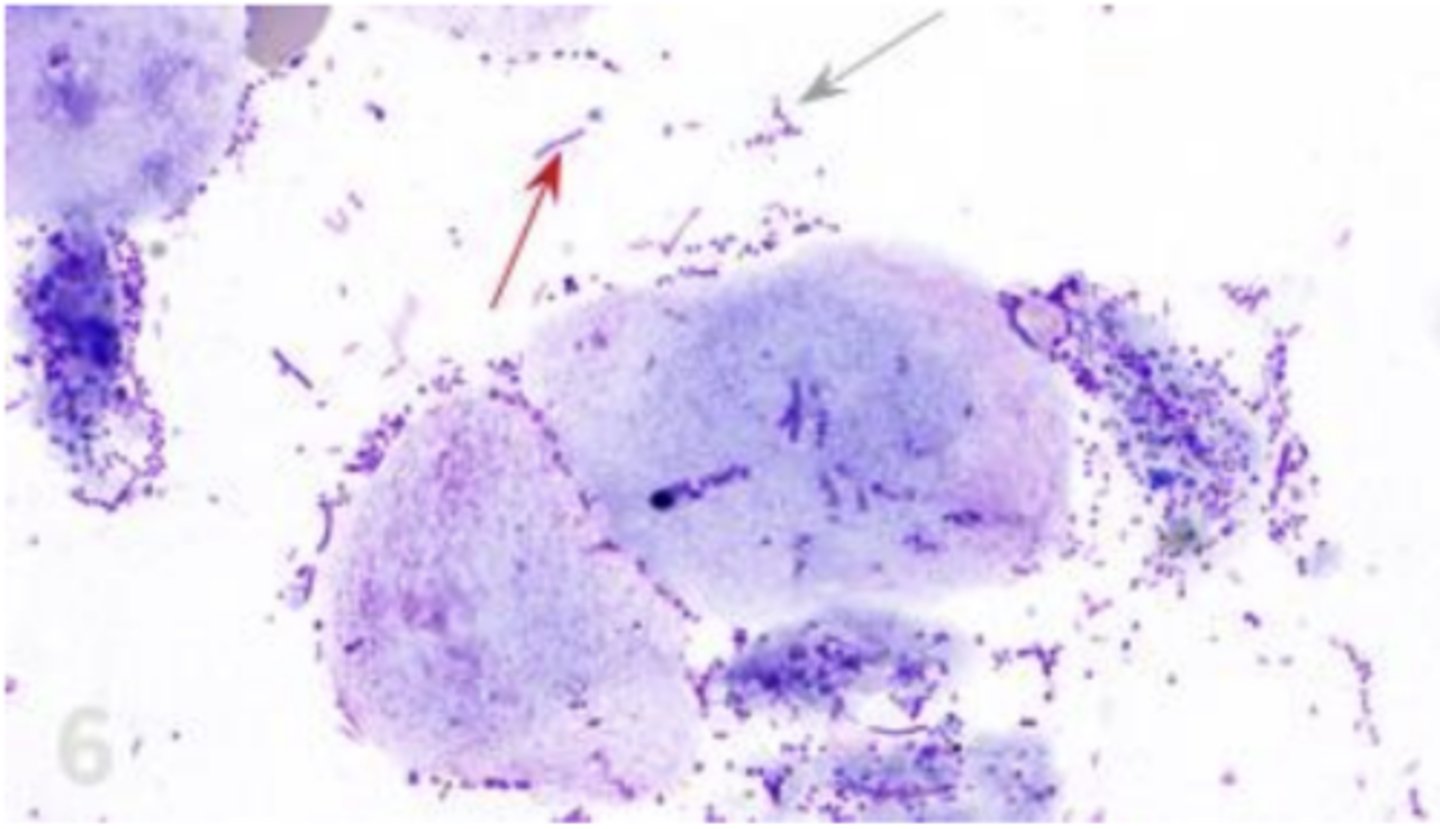

What is it? At red arrows

Eosinophils